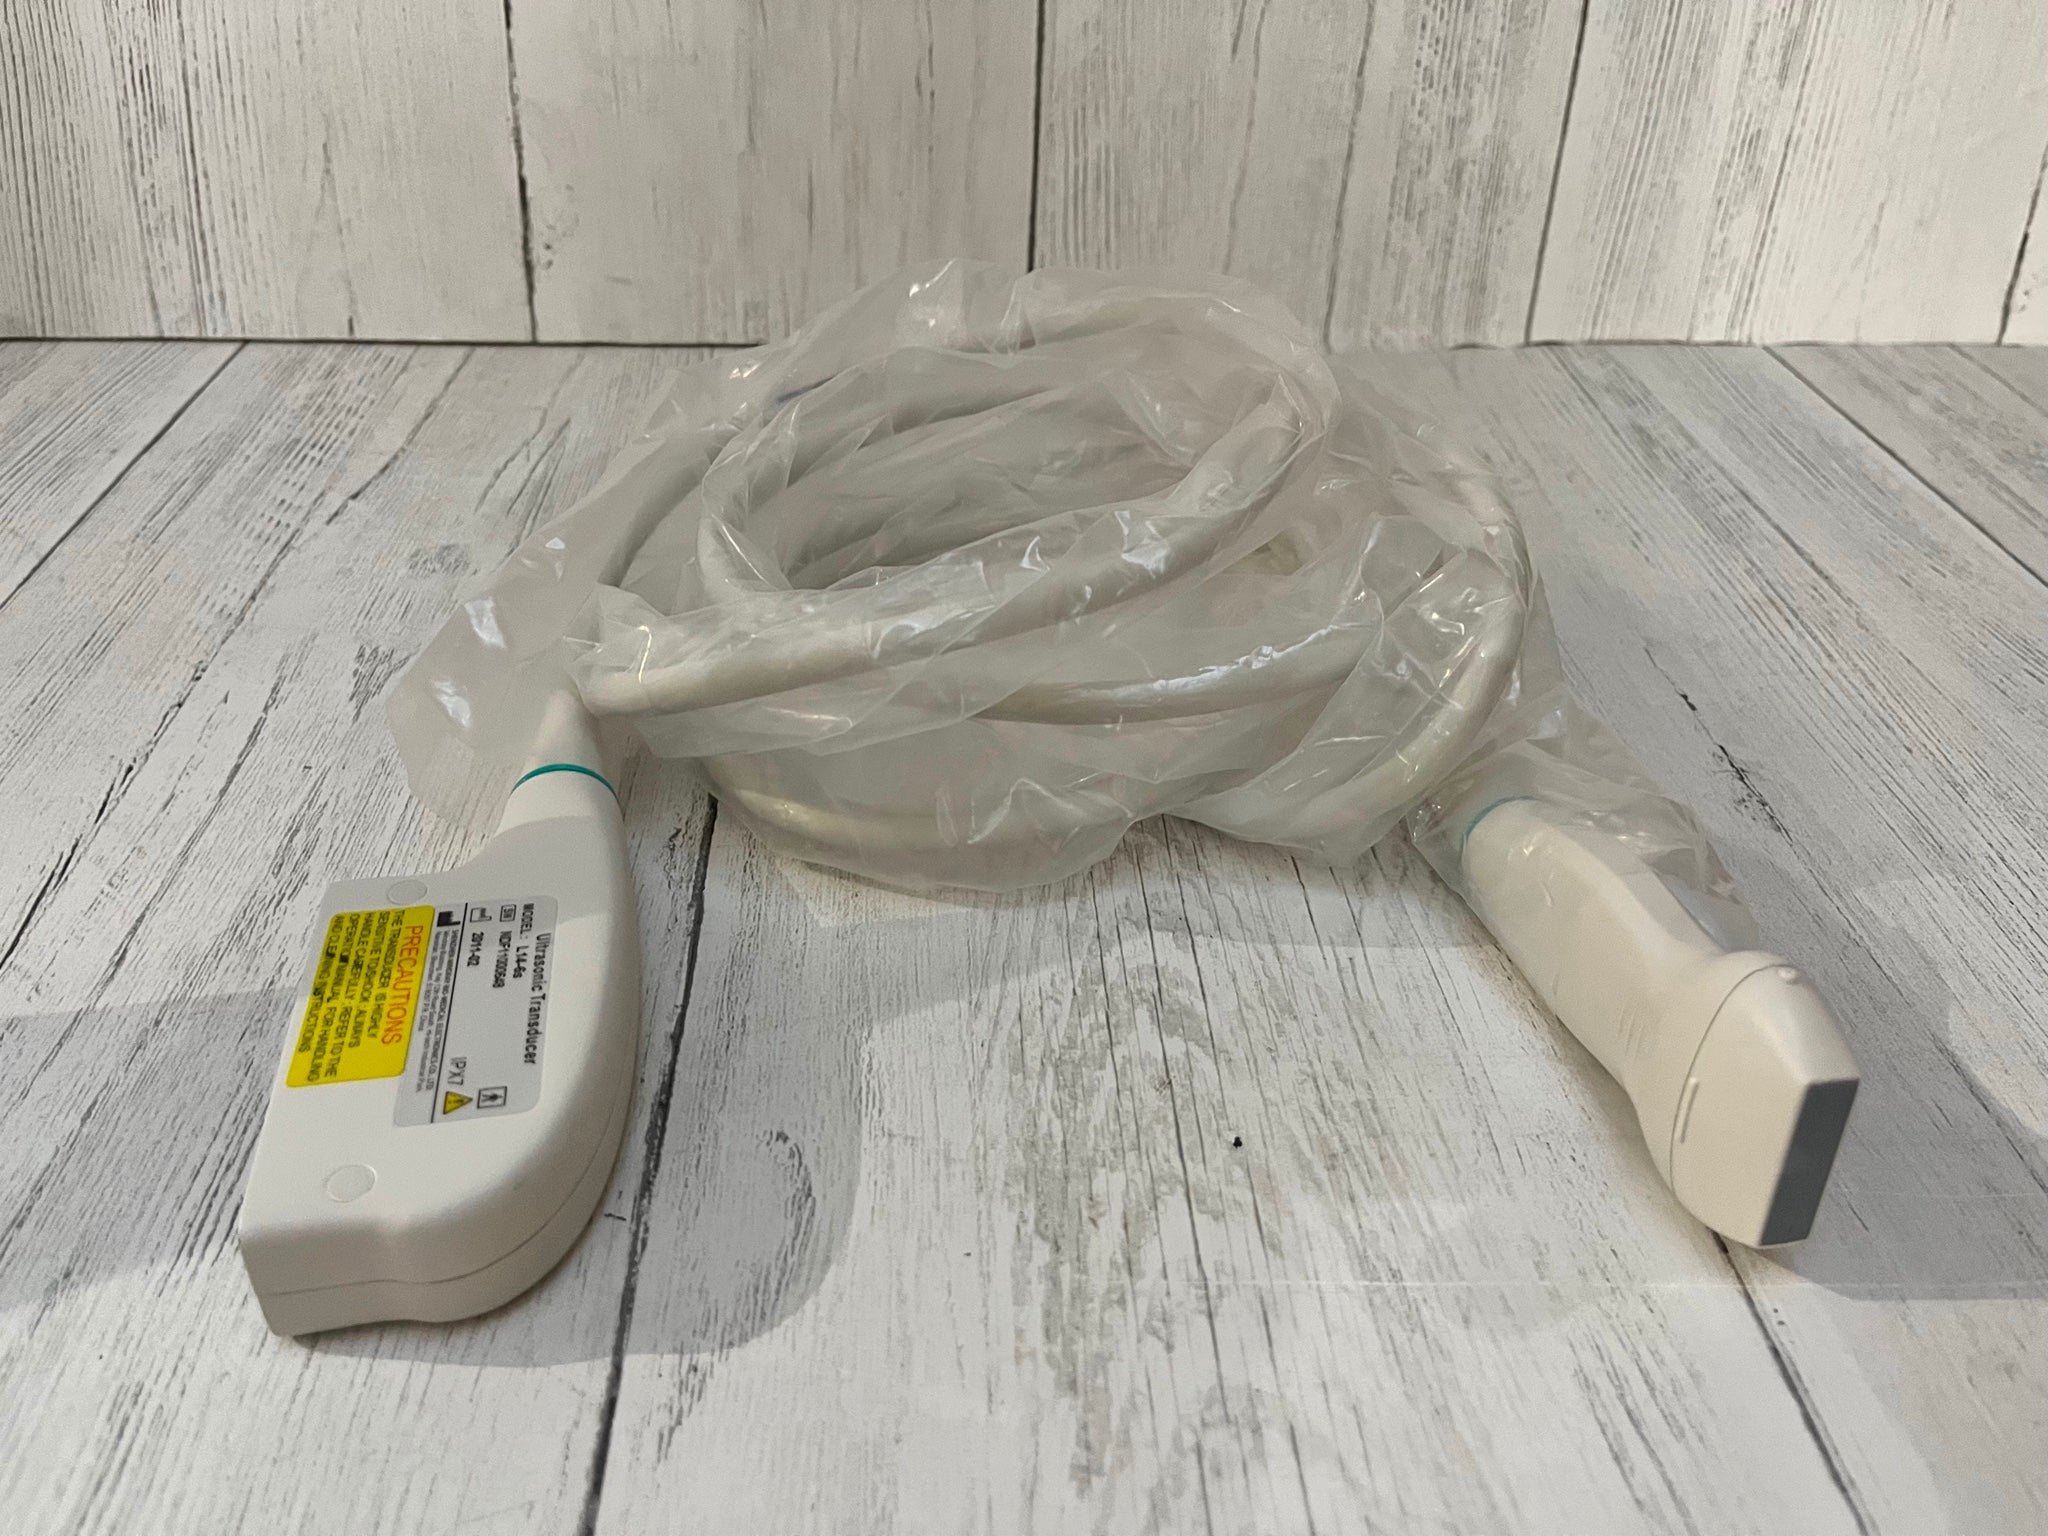

Our portable ultrasound scanner is equipped with cutting-edge technology that improves diagnostic accuracy. With its convex linear transvaginal probe, it allows for detailed imaging of internal structures. The tool is designed to be user-friendly, meaning healthcare professionals can easily operate it without extensive training. Therefore, its advanced features can help in making quick and informed decisions in clinical settings, which is essential for patient care.

The scanner’s compact design makes it highly portable, allowing healthcare providers to conduct examinations in various settings. Whether it is a clinic or a hospital, this ultrasound machine can be easily transported. Healthcare professionals appreciate its lightweight structure, so they can perform immediate diagnostics without being tied to a fixed location. Because of its convenience, this device enhances the delivery of healthcare services.